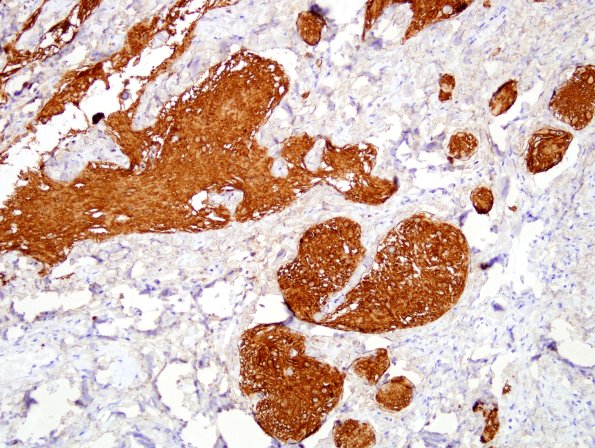

Glial cells are prominent in the specimen as demonstrated by GFAP immunohistolocalization. (GFAP IHC)